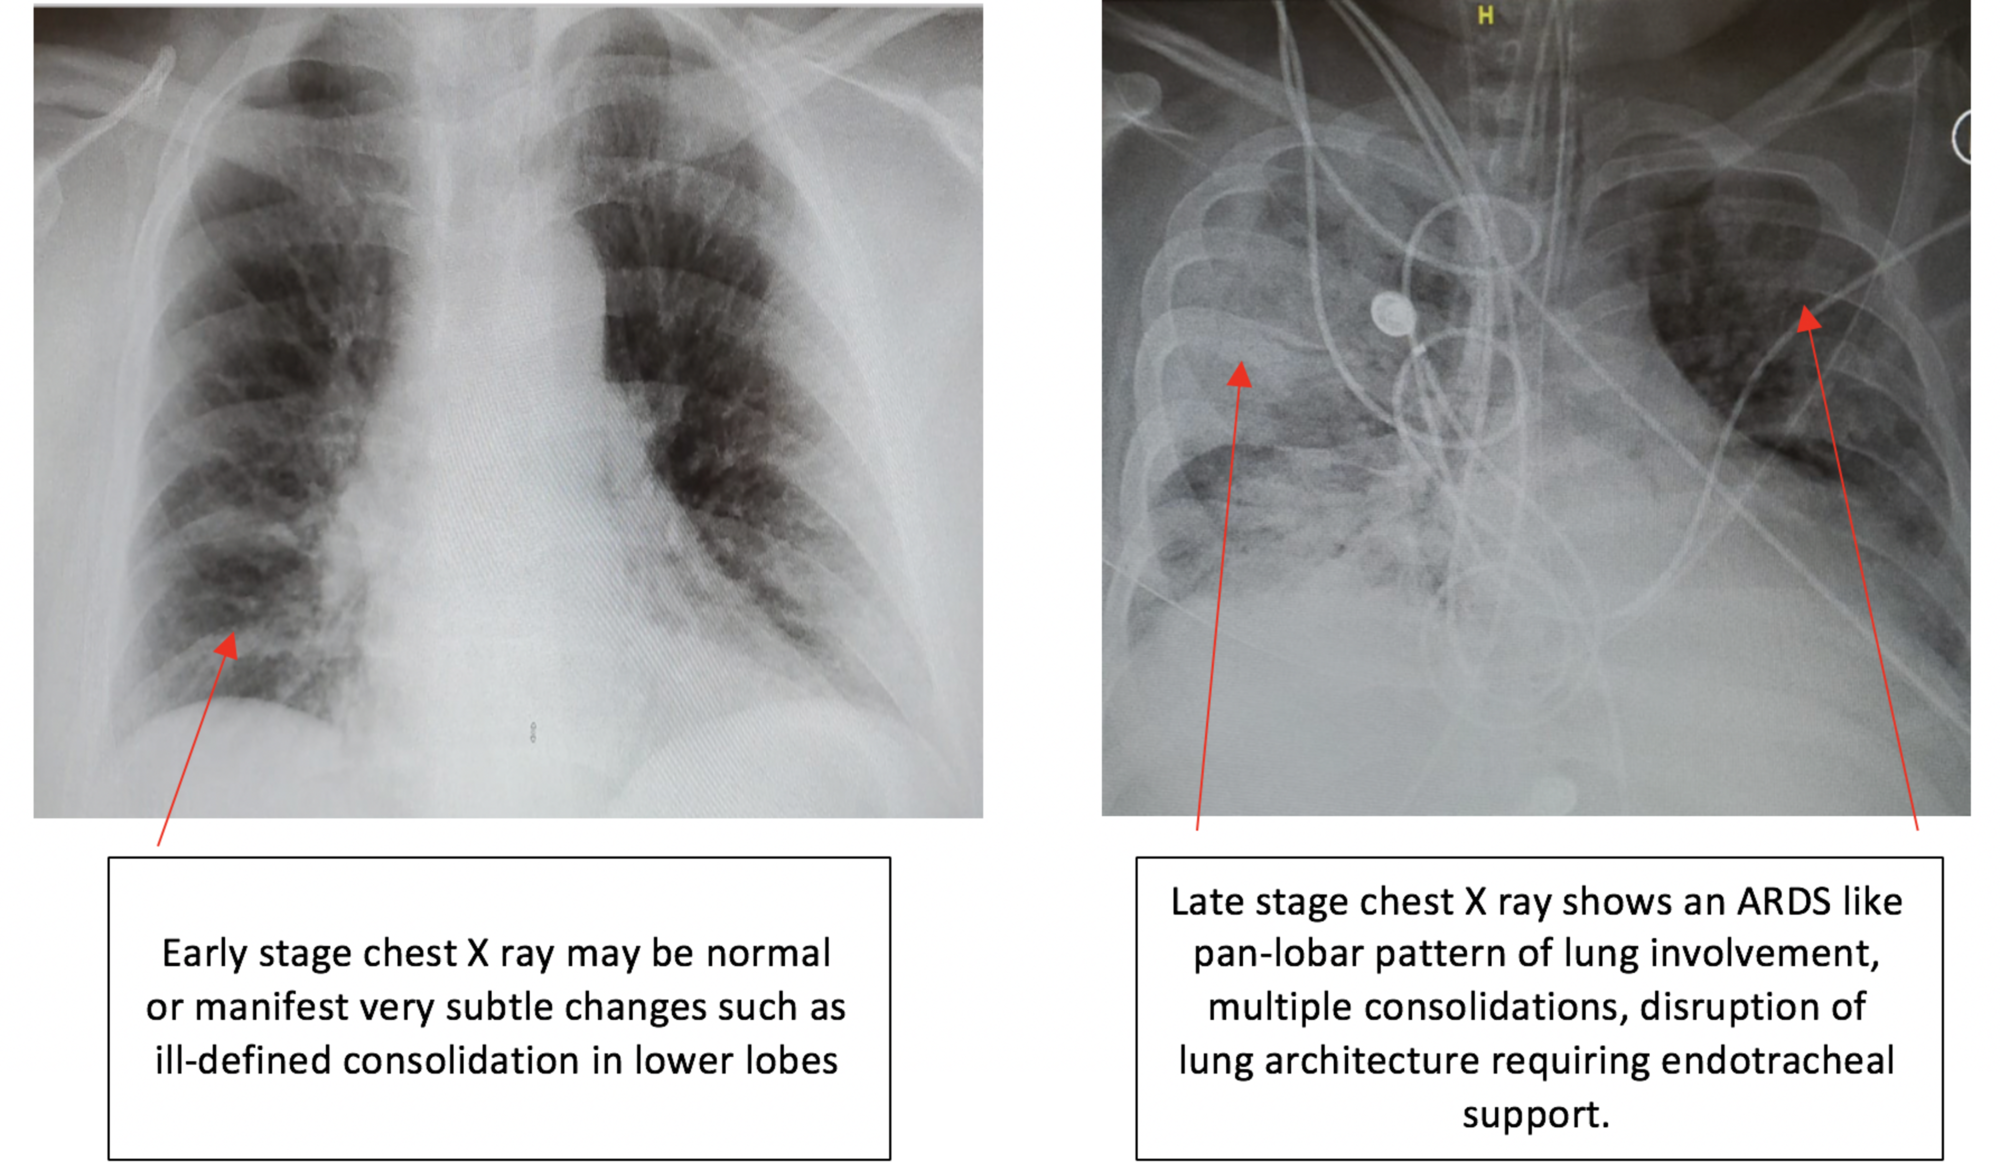

Chest x-ray findings in early and late stages of Covid-19